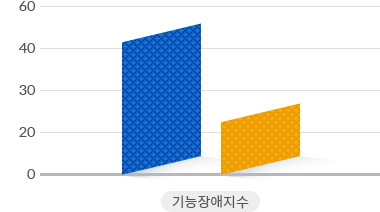

척추관협착증 수술 VS 비수술 치료 기능장애 변화 비교

수술치료

수술치료

비수술치료

비수술치료